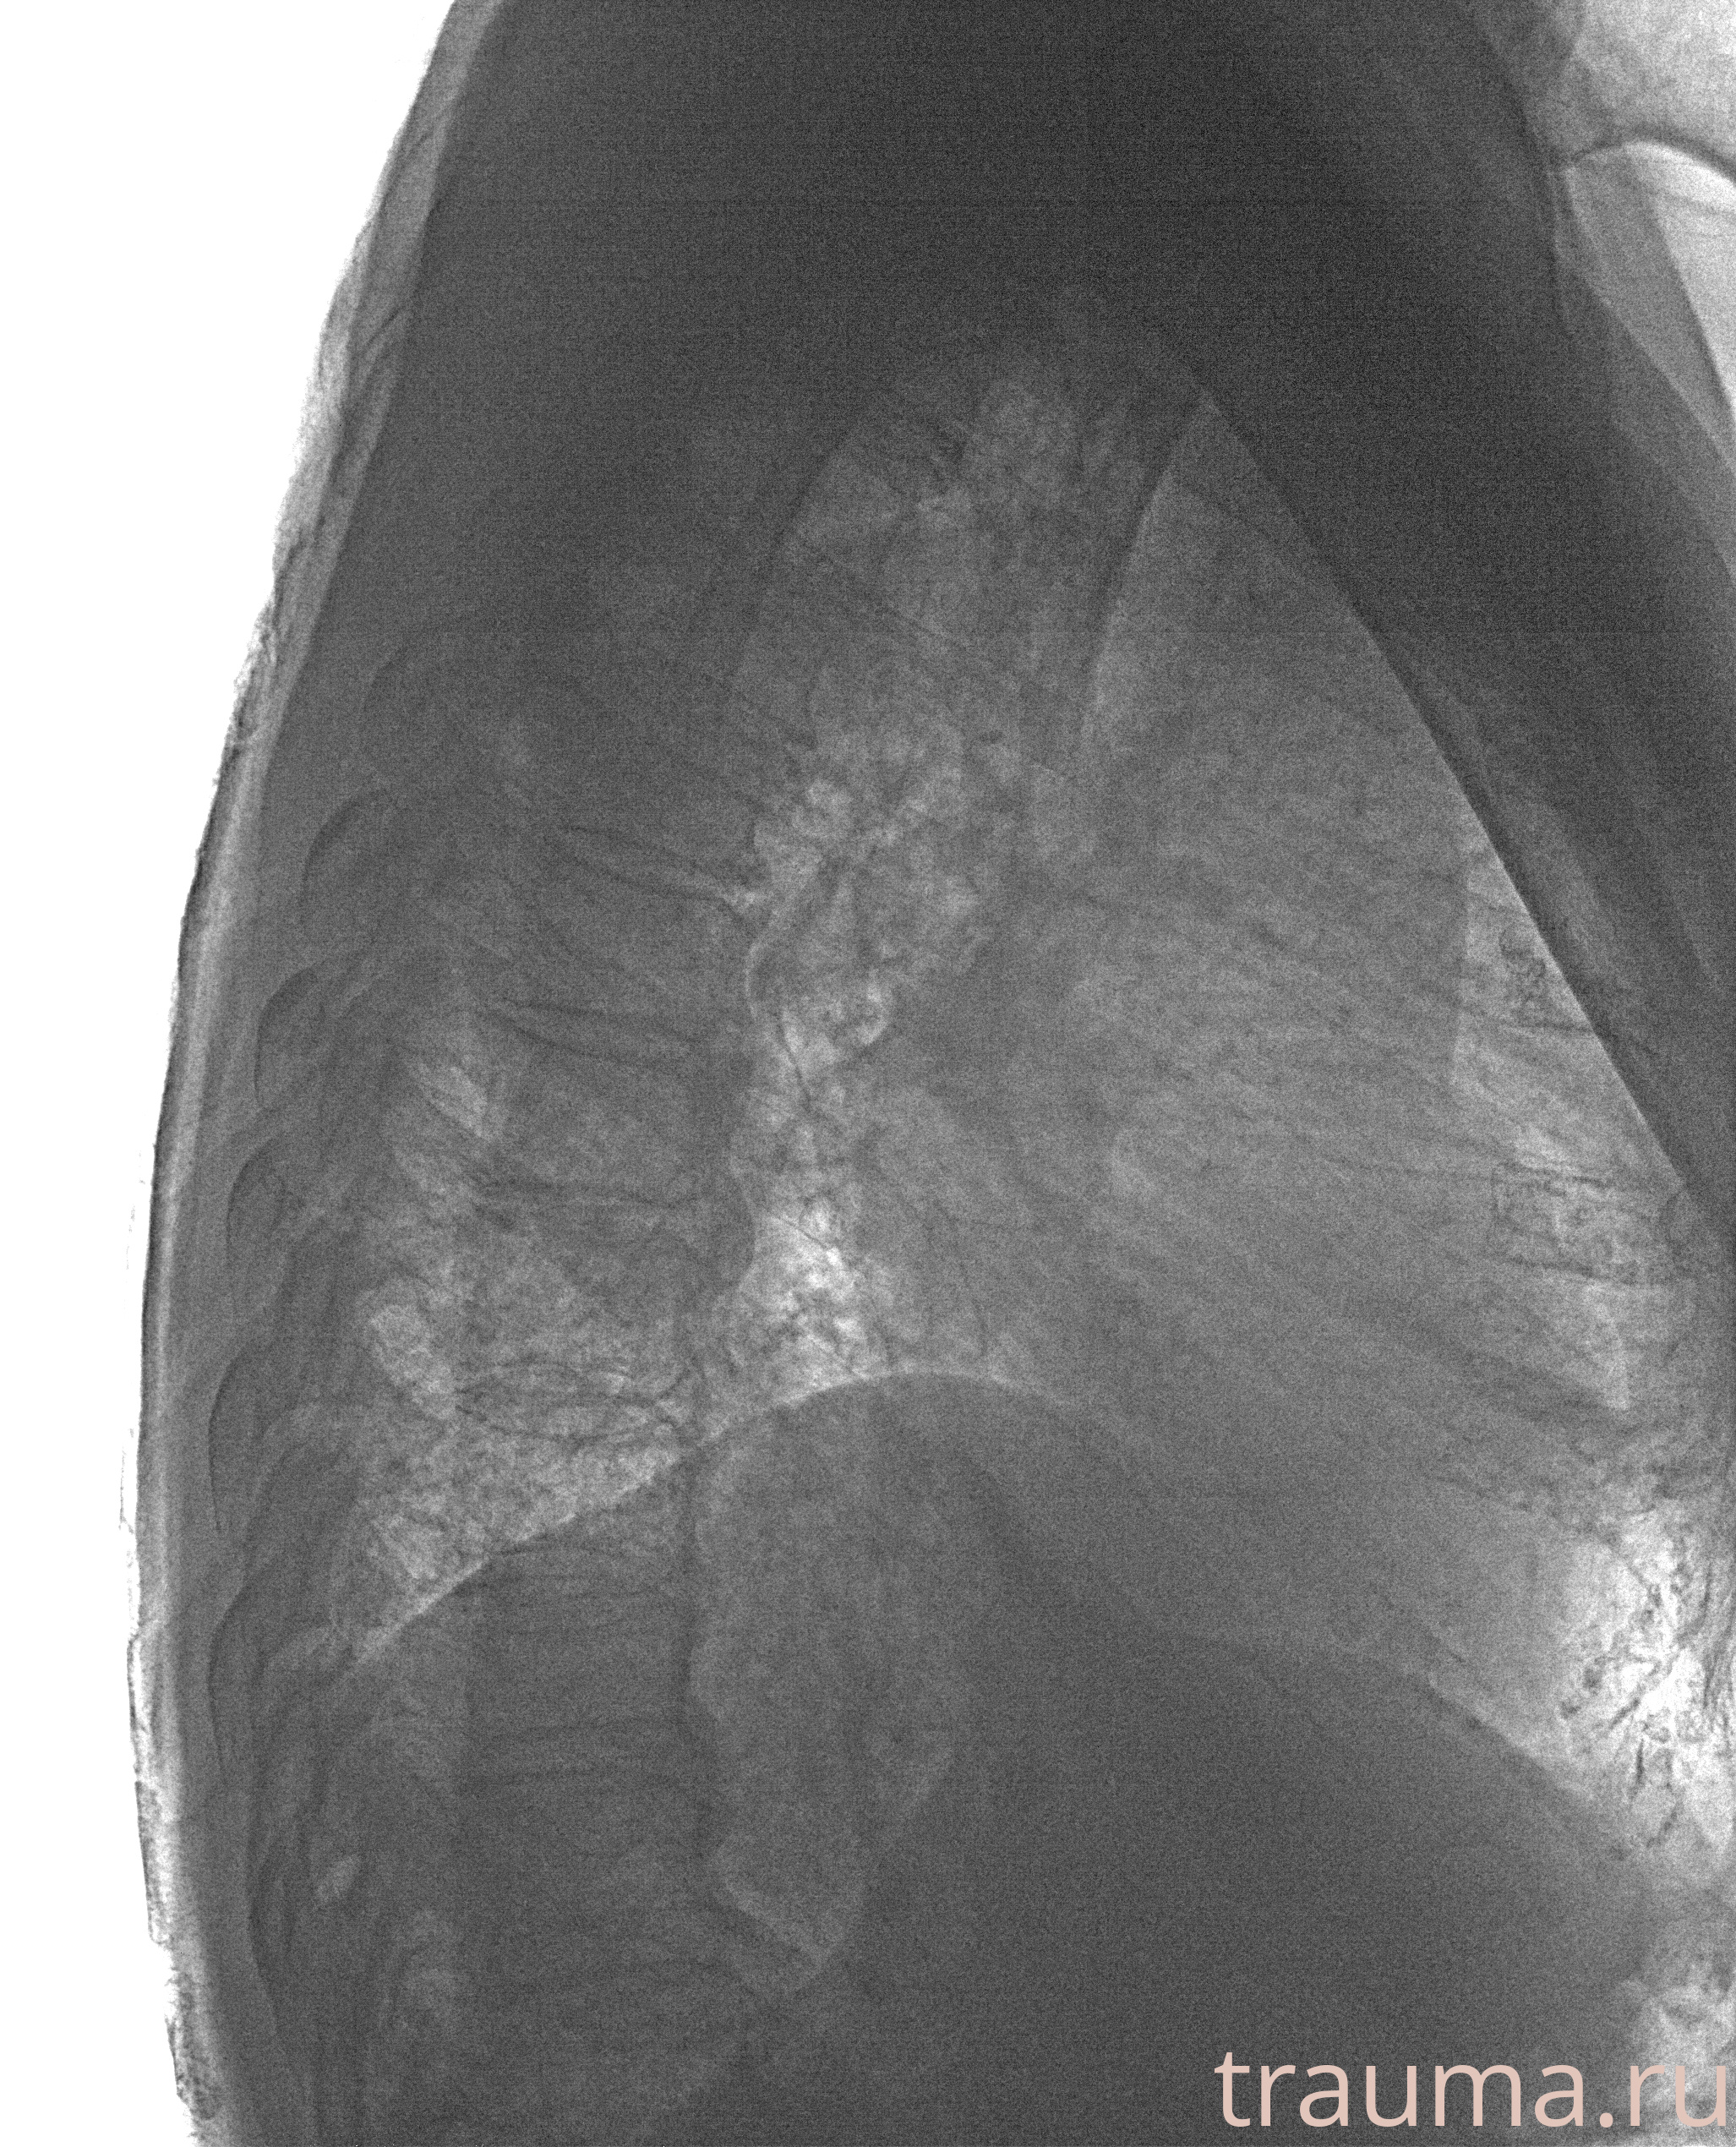

Рентген на дому: по вашему адресу приезжает врач-рентгенолог, травматолог-ортопед с мобильным рентгеновским аппаратом, проводит диагностику травмы или заболевания, делает необходимые рентгенограммы, дает рекомендации по дальнейшему лечению. Получить качественные снимки в домашних условиях возможно благодаря уникальной методике, разработанной МосРентген Центром для института  Склифосовского